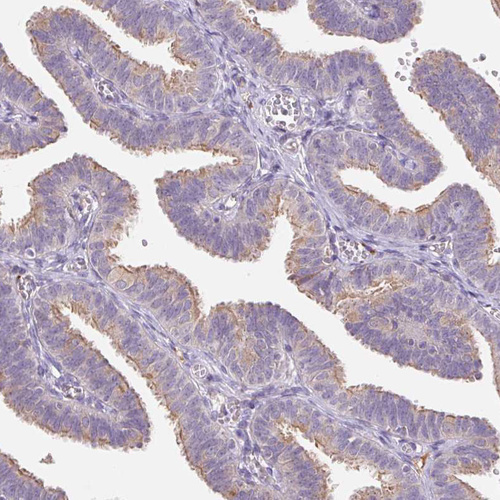

Immunohistochemical staining of human Fallopian tube moderate membranous positivity in glandular cells.